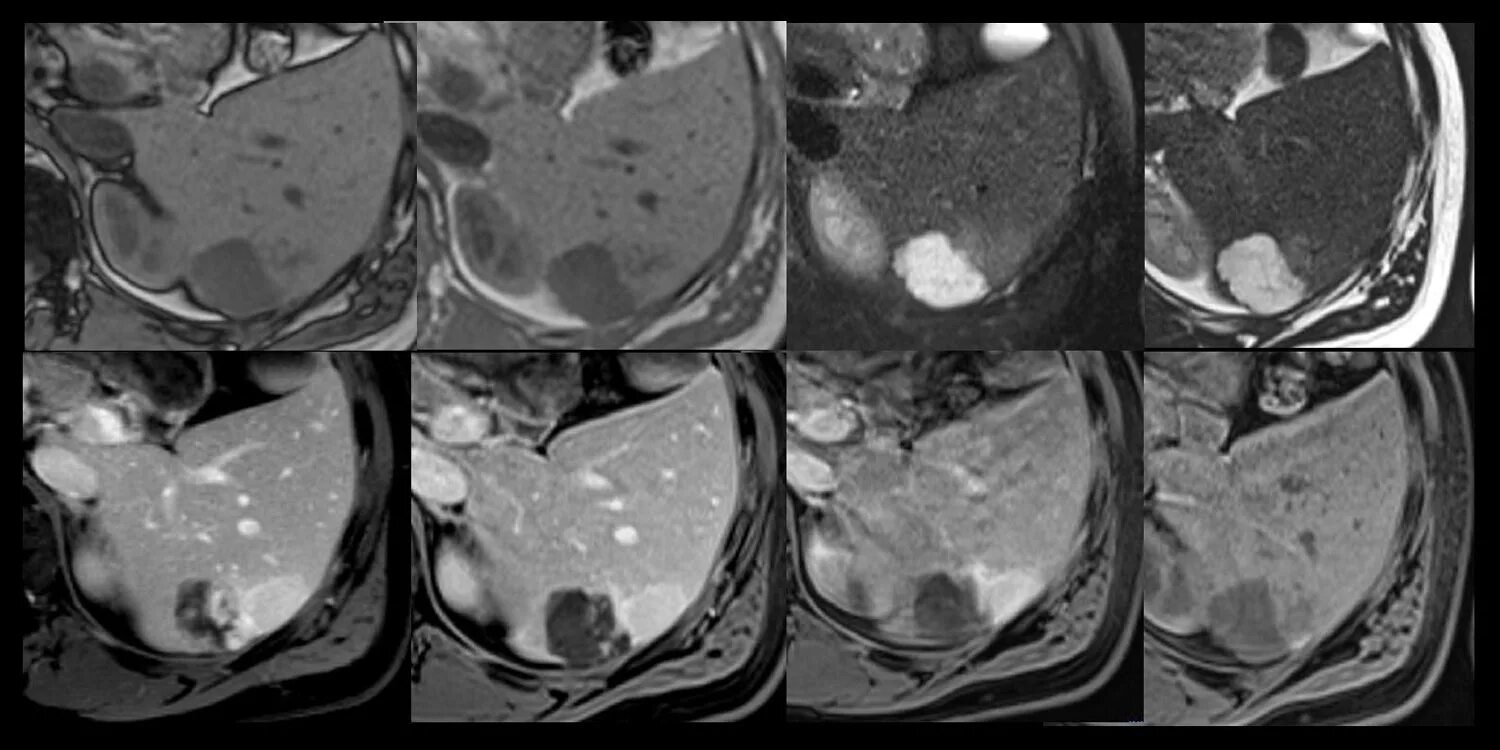

Цирроз на кт